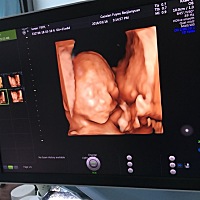

能看出是男孩女孩吗?

姐妹们,猜猜是男孩,女孩,